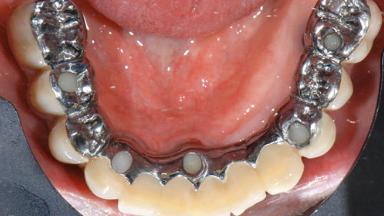

Repeated Acrylic Fractures on a Mandibular Fixed Full-arch Implant-supported Metal/Acrylic Prosthesis

A 77-year-old male patient was referred for the management of frequent and repeated acrylic fracture of his existing mandibular fixed full-arch implant-supported metal/acrylic prosthesis. He also complained about softtissue soreness and the lack of retention and stability of his maxillary removable partial metal/acrylic prosthesis. Both prostheses had been delivered two years previously as part of his full-mouth rehabilitation (caries, tooth wear, tooth fracture). His medical history revealed high blood pressure, controlled with the use of antihypertensive medication.

Retention Screw-retained, with 4 or more splinted implants Screw-retained, with 4 or more splinted implants